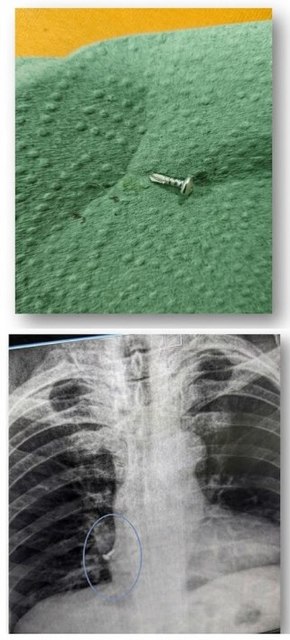

Саморіз на виробництві: Дорослий чоловік під час роботи випадково вдихнув металевий саморіз. Допомога була надана амбулаторно: наші фахівці швидко вилучили стороннє тіло з бронхів.